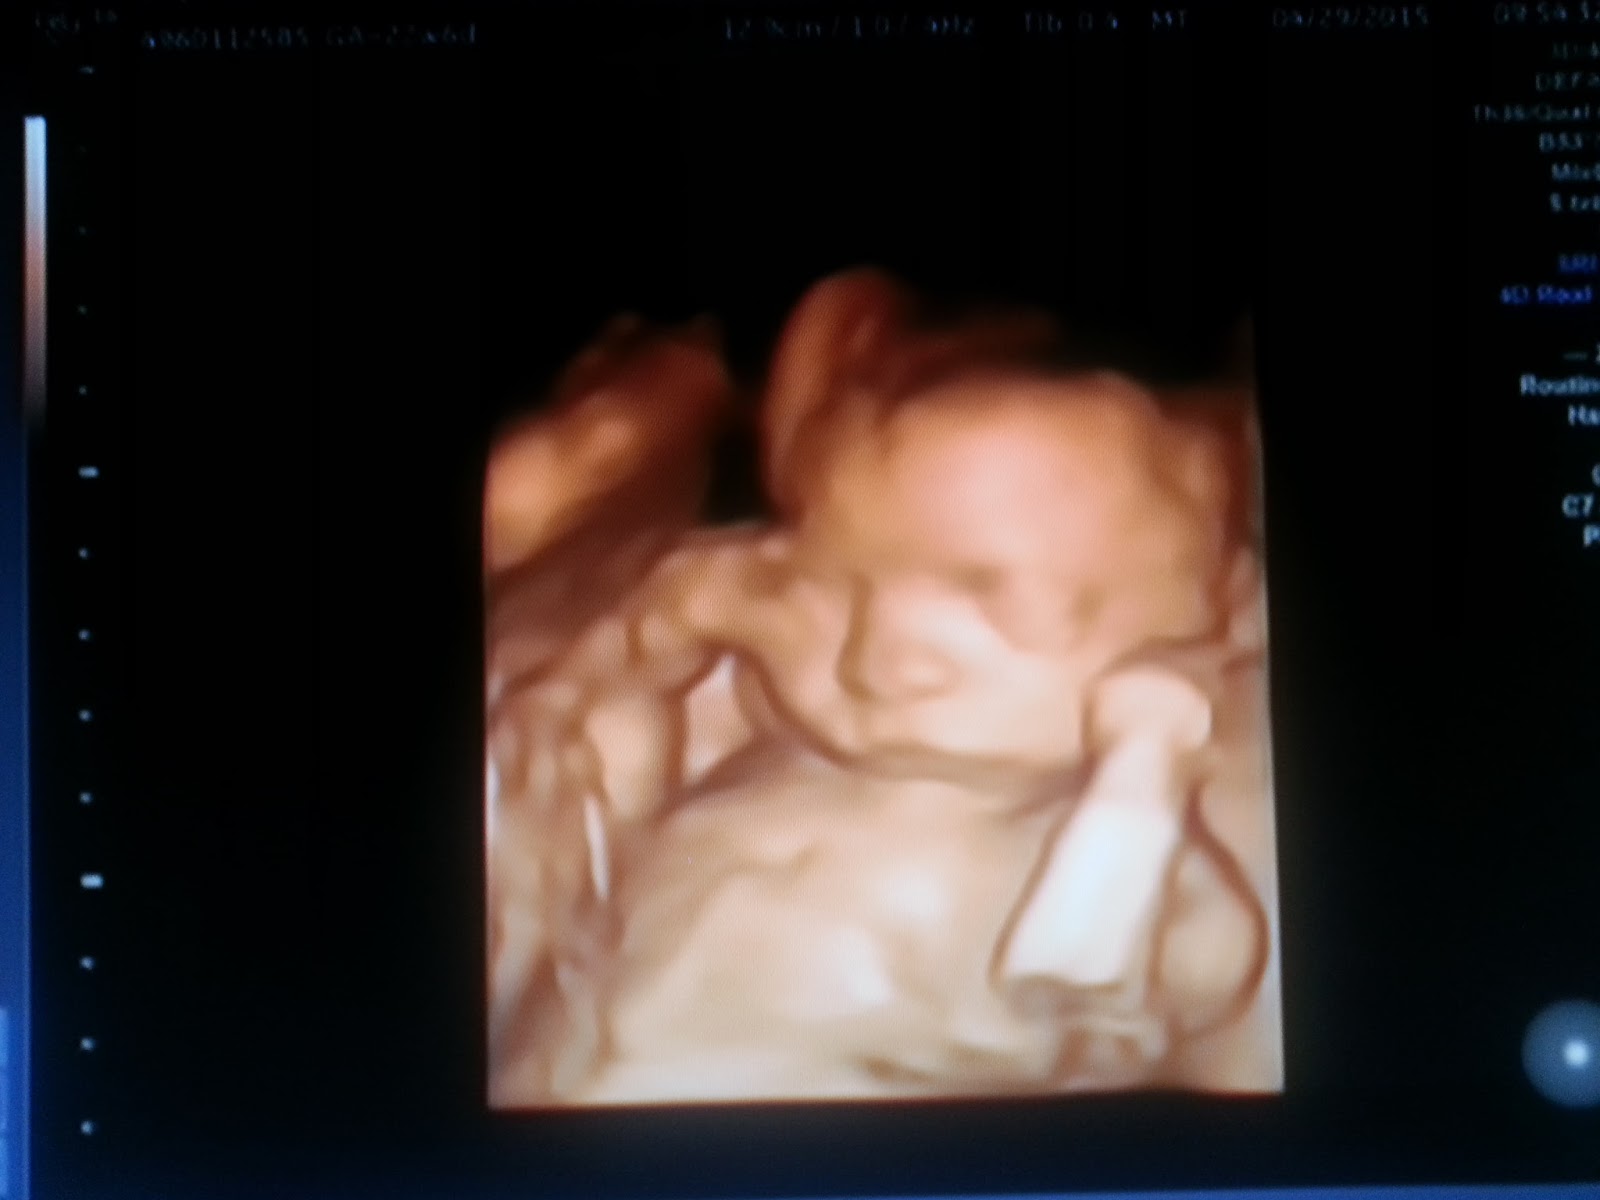

23 Weeks Pregnant 3d

3d Baby Ultrasound Scan What To Expect Huggies

23rd Week 4d Ultrasound Amazing Youtube